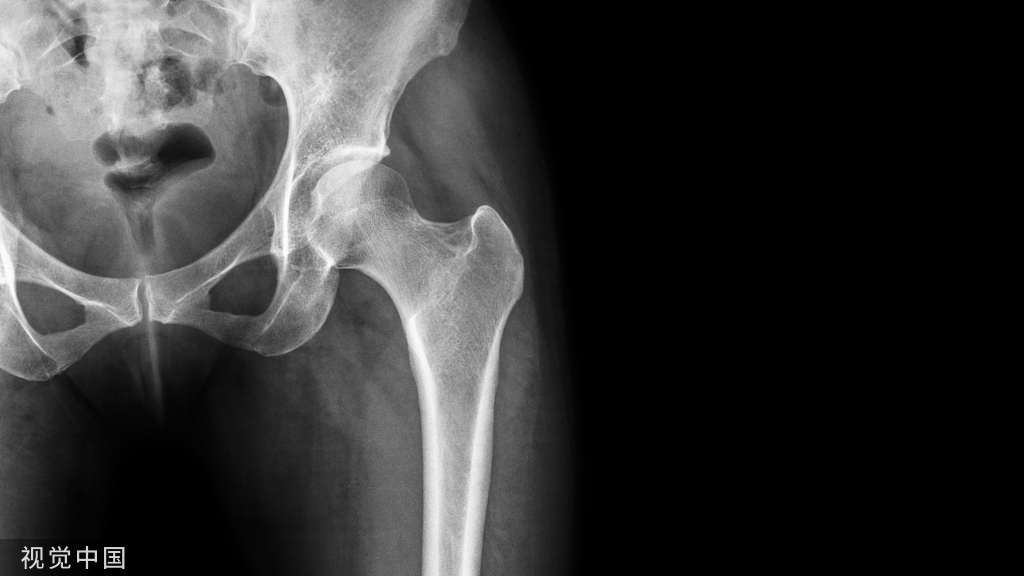

一般来说,从前方 ORIF 就可完成后柱固定,在大多数情况,标准的前方入路可直接或间接复位后 Pilon 骨折。当 Pilon 骨折后柱严重粉碎时,可选择后方入路,通过直接纠正后柱的长度、成角及旋转,为前方骨折复位提供参考。

后外侧入路应用相对较多。Pilon 骨折一般选择俯卧位,踝关节后方骨折时可选择同侧臀部垫高仰卧位。该入路只能通过复位后外侧骨块间接恢复后方关节面,一些主要骨折块在后方时也可直接复位干骺端,恢复长度与旋转;整复完整的后方平台也可为前方骨折复位提供参考。